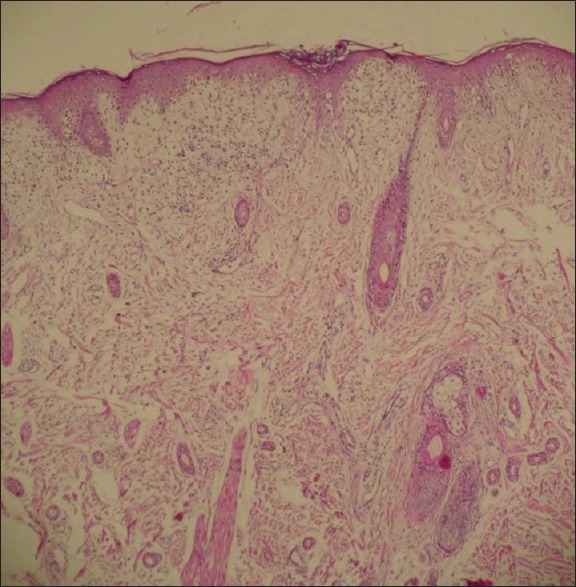

The patient is a 6-month-old infant who presented with annular erythematous plaques with mild scaling on the face, especially forehead and around the eyes, gradually spreading to the neck, trunk and extremities since 4 months ago [Figures 1-3]. Its general health has been good and he had no problems at birth. The patient has been the first child of the family, with a history of pain in the joints of hand in the mother from about 3 years ago without citing a specific diagnosis. Skin biopsy was taken from the infant, which showed vacuolar changes in the epithelial basement membrane in dermoepidermal junction and in the epithelial junction of the appendages with necrotic keratinocytes, perivascular and periadnexal infiltrates with lymphocyte predominance and precipitation of dermal mucin [Figures 4 and 5].

Figure 4.

Hydropic degeneration of basal keratinocytes, dermal edema and a superficial lymphohistiocytic chronic inflammatory cell infiltrate (H and E, ×40)

Biopsy of the skin lesions tends to be similar to SCLE rash, and is seen in two forms: Desquamative erythmatous and wheal-like lesions. The main findings include vacuolar changes in the epithelial basement membrane in the dermoepidermal junction and in the epithelial junction of appendages with necrotic keratinocytes, perivascular and periadnexal infiltrates with lymphocyte predominance and precipitation of dermal mucin.[7]